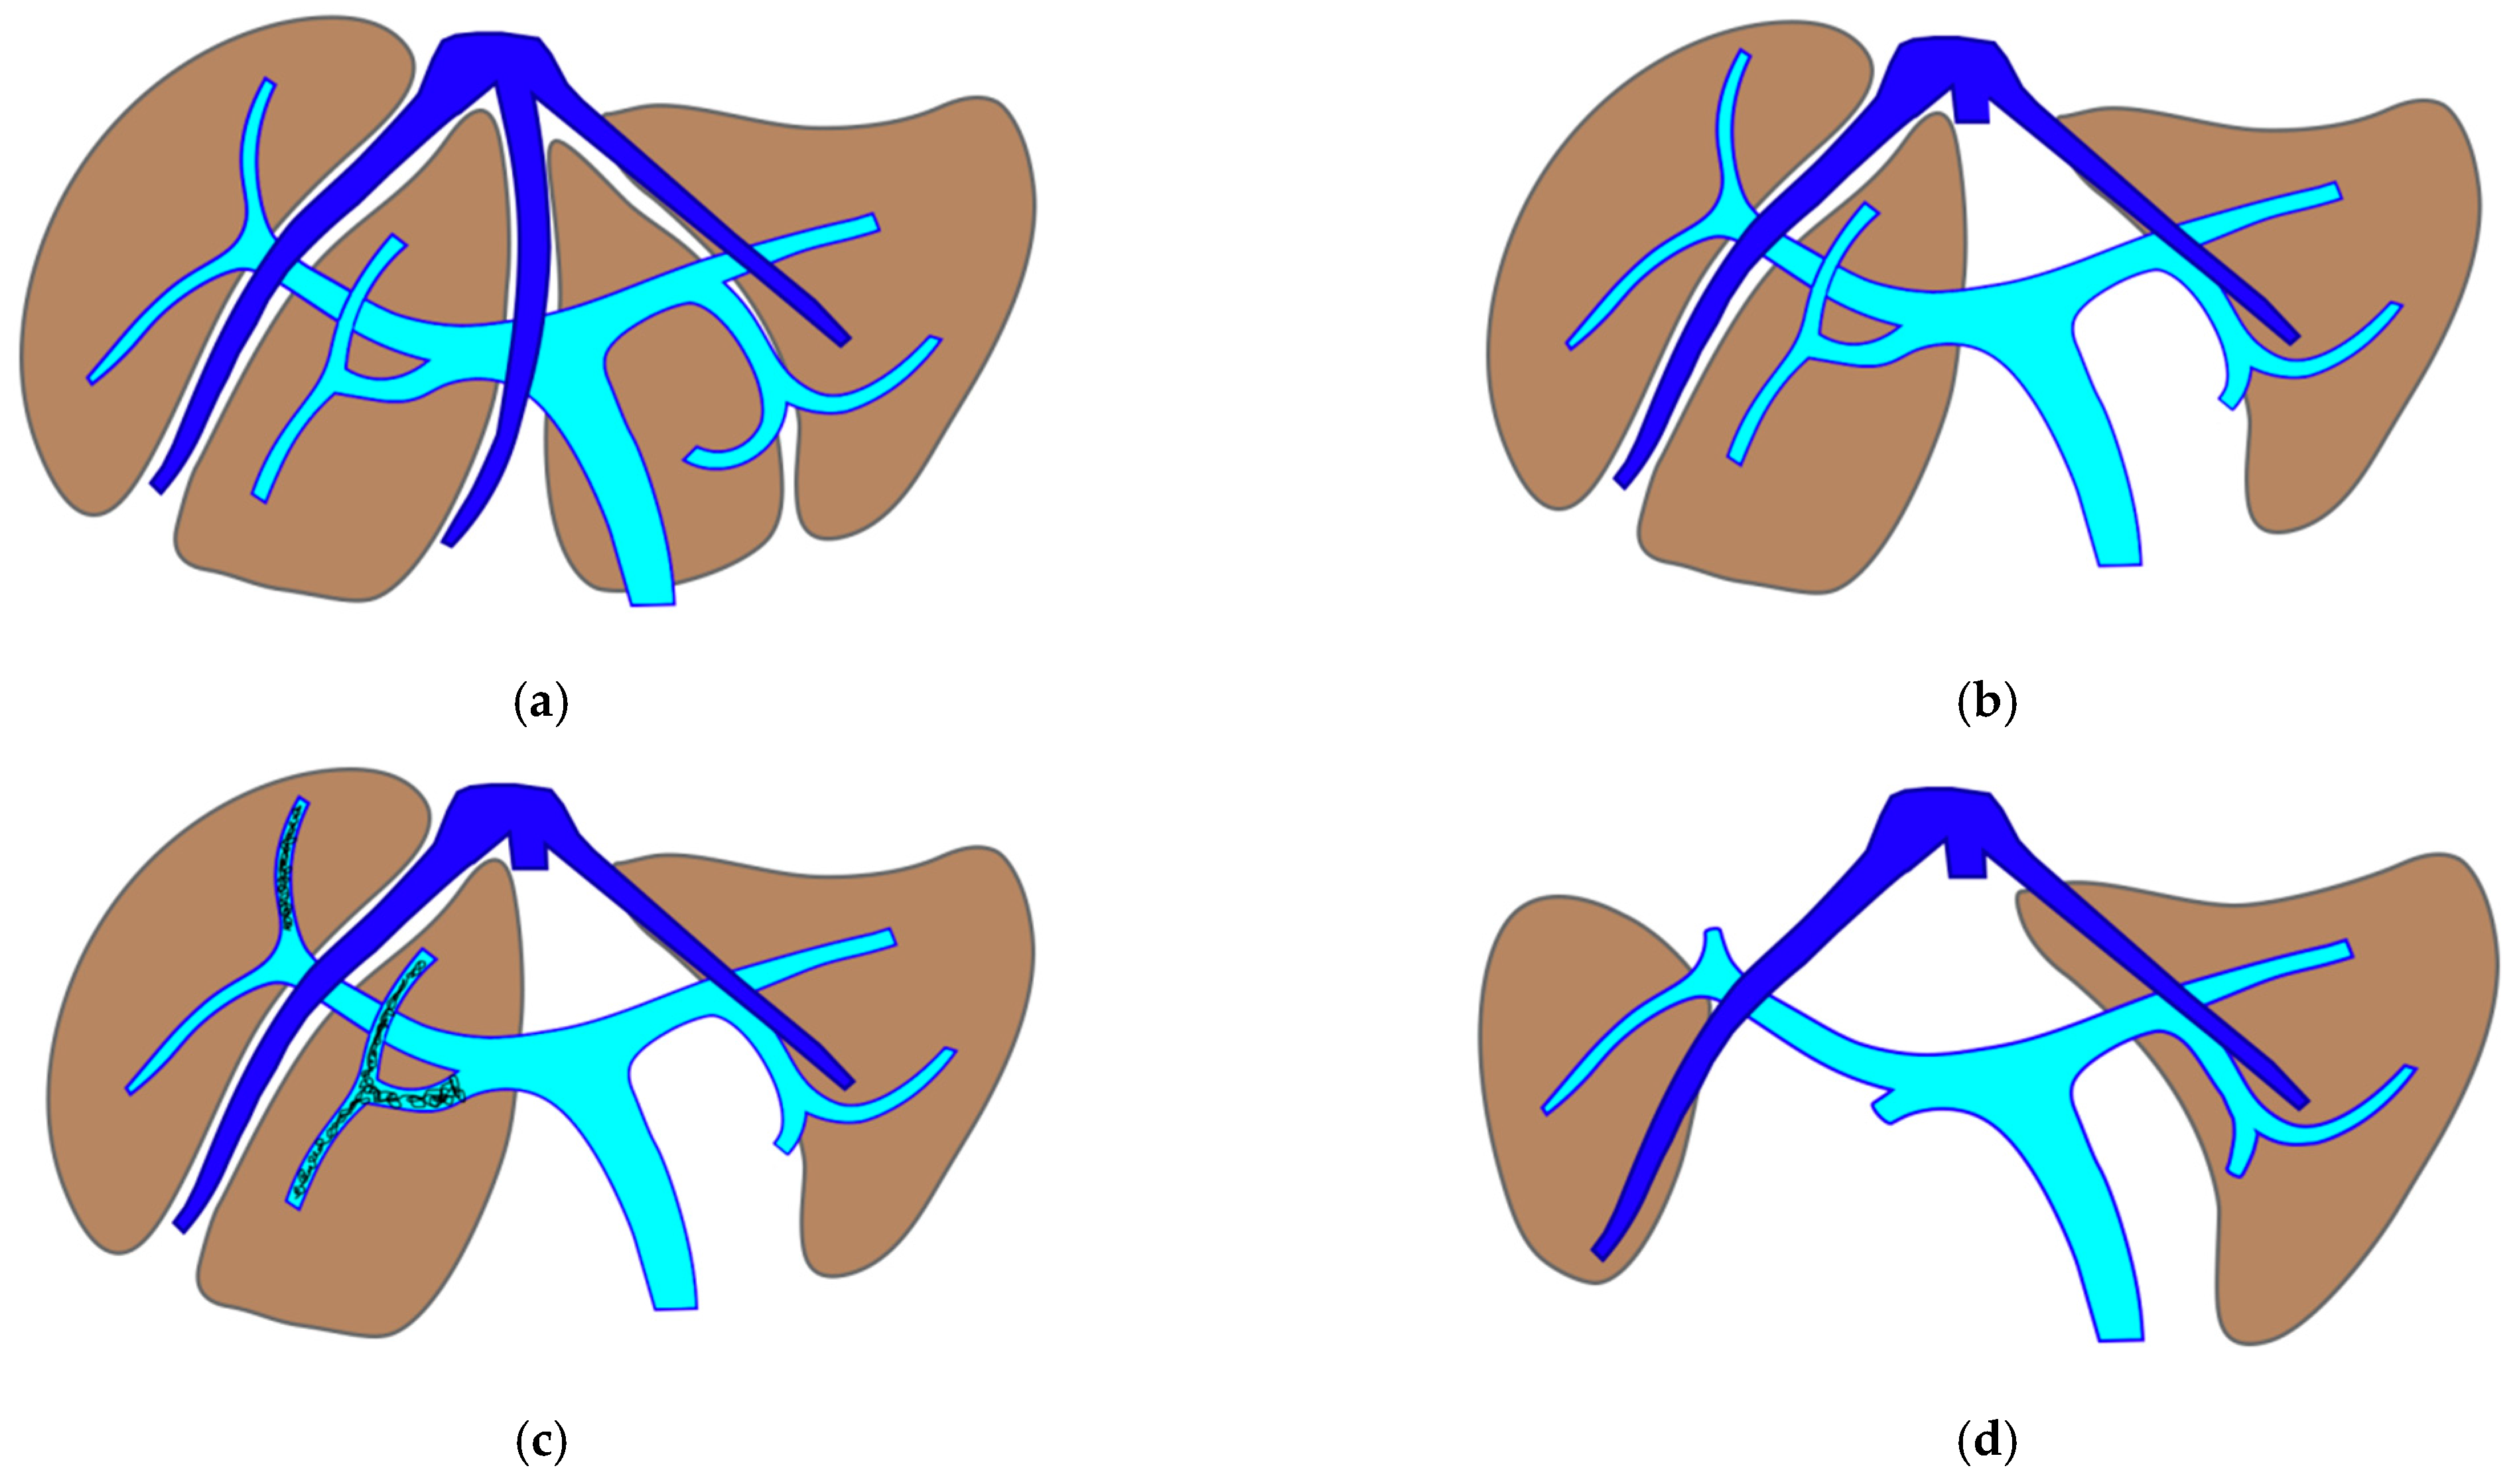

The TWO-STAGE major PSH with SS-PVE is proposed when preservation of a second-order GP is planned and FLR volume is less than 40%. The first-stage procedure is MLP with resection of CRLM at the hepatocaval confluence and in one of the two livers. After this first stage, the SS-PVE is performed in the liver with CRLM still in place. At stage two, the embolized liver and all residual CRLMs are resected with a vessel-guided parenchyma-sparing technique. At the end of the second stage, both livers are preserved. The TWO-STAGE hepatectomy is defined as parenchyma sparing (PS) because it aims at preserving a single liver segment in the right liver instead of performing extended right hepatectomy. See Figure 1.

Figure 1. PS-TSH with SS-PVE. The parenchyma-sparing TWO-STAGE major hepatectomy with super-selective PVE is proposed when preservation of a second-order GP is planned and FLR volume is less than 40%. (a) Whole liver. (b) First stage: vessel-guided mesohepatectomy of S1/S4 en-bloc with MHV for liver partition (MLP). (c) Super-selective PVE of the anterior portal branch for S5/S8 and of the portal branch for S7, preserving the portal branch for S6. (d) Second stage: vessel-guided resection of embolized liver. At the end of PS-TSH there are two livers: one on the right constituted by S6, and one on the left constituted by S2/S3. Abbreviations: PS: parenchyma sparing; TSH: two-stage hepatectomy; SS-PVE: super-selective portal vein embolization; GP: glissonean pedicle; FLR: future liver remnant; MHV: middle hepatic vein; MLP: mesohepatectomy for liver partition; S: segment.